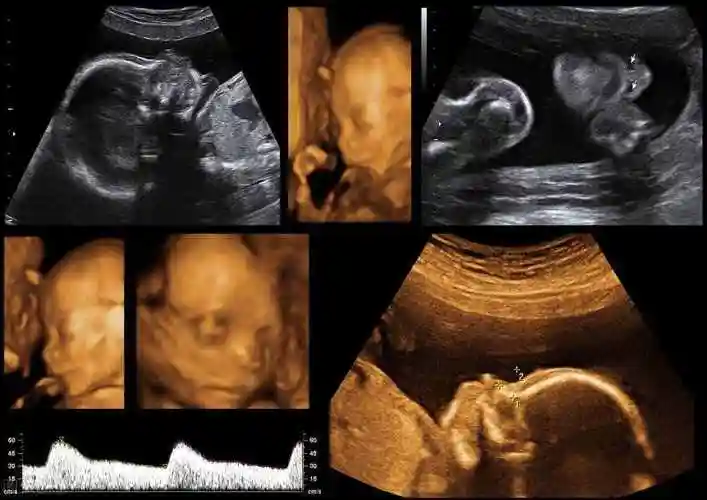

胎儿四维照为何丑哭?"头大腿短"暗示什么?孕期四维必备知识点